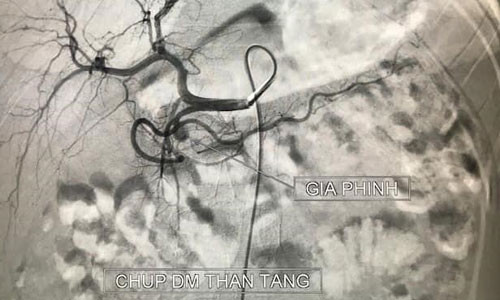

Khi vào viện, bệnh nhi này nôn máu nhiều lần không tự cầm. Phim chụp cắt lớp vi tính cho thấy ổ giả phình lớn động mạch vị tá tràng (có chức năng cung cấp máu cho tá tràng - tụy và dạ dày).

| Hình ảnh ổ giả phình lớn động mạch vị tá tràng ở bệnh nhân. Ảnh: BVCC. |

Sau 20 phút can thiệp với 5 coils ổ giả phình đã được loại bỏ hoàn toàn. Bệnh nhi hết nôn ra máu, huyết động ổn, sau đó được chuyển về khoa Nhi tiếp tục điều trị tình trạng viêm tụy cấp.